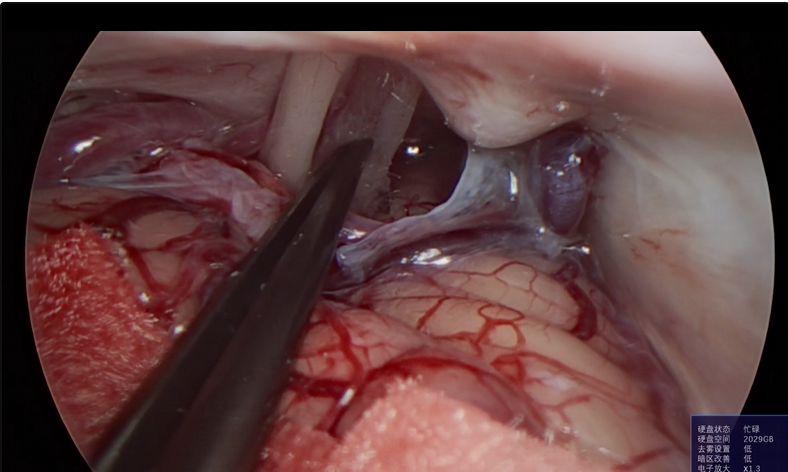

神经外科垂体瘤手术